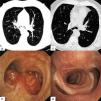

A 69-years-old male patient, non-smoker, with exertional dyspnea for the last 6 months, underwent a chest CT scan that revealed a large tumor mass under the carina with endobronchial involvement and obstruction of both main bronchi (Fig. 1a). Bronchoscopy showed two lobulated endobronchial masses protruding on each side of the main carina, with a bright, smooth, and highly vascularized surface. The masses extended 3cm to the proximal segment of both main bronchi, producing a 90% bronchial lumen obstruction (Fig. 1b). The endobronchial component was treated with LASER photocoagulation and mechanical resection with significant desobstruction and symptom improvement. Histopathology revealed a benign schwannoma (fusiform cells with S100 expression). Definitive treatment consisted of carinal resection with reconstruction of a neocarina between the trachea and right and left main bronchi. Bronchoscopy 18 months after surgery showed a narrow right upper bronchus, straight intermediate bronchus, a S-shaped neocarina with a shifted left main bronchus (Fig. 1c and 1d). Endobronchial schwannoma is a rare entity, accounting for just 2% of benign tracheobronchial tumors. These tumors may affect any part of the tracheobronchial tree, with intra or extraluminal involvement.1 Clinical presentation depends on the tumor size and location. Treatment consists of surgical resection, especially in tumors with extraluminal extension.2